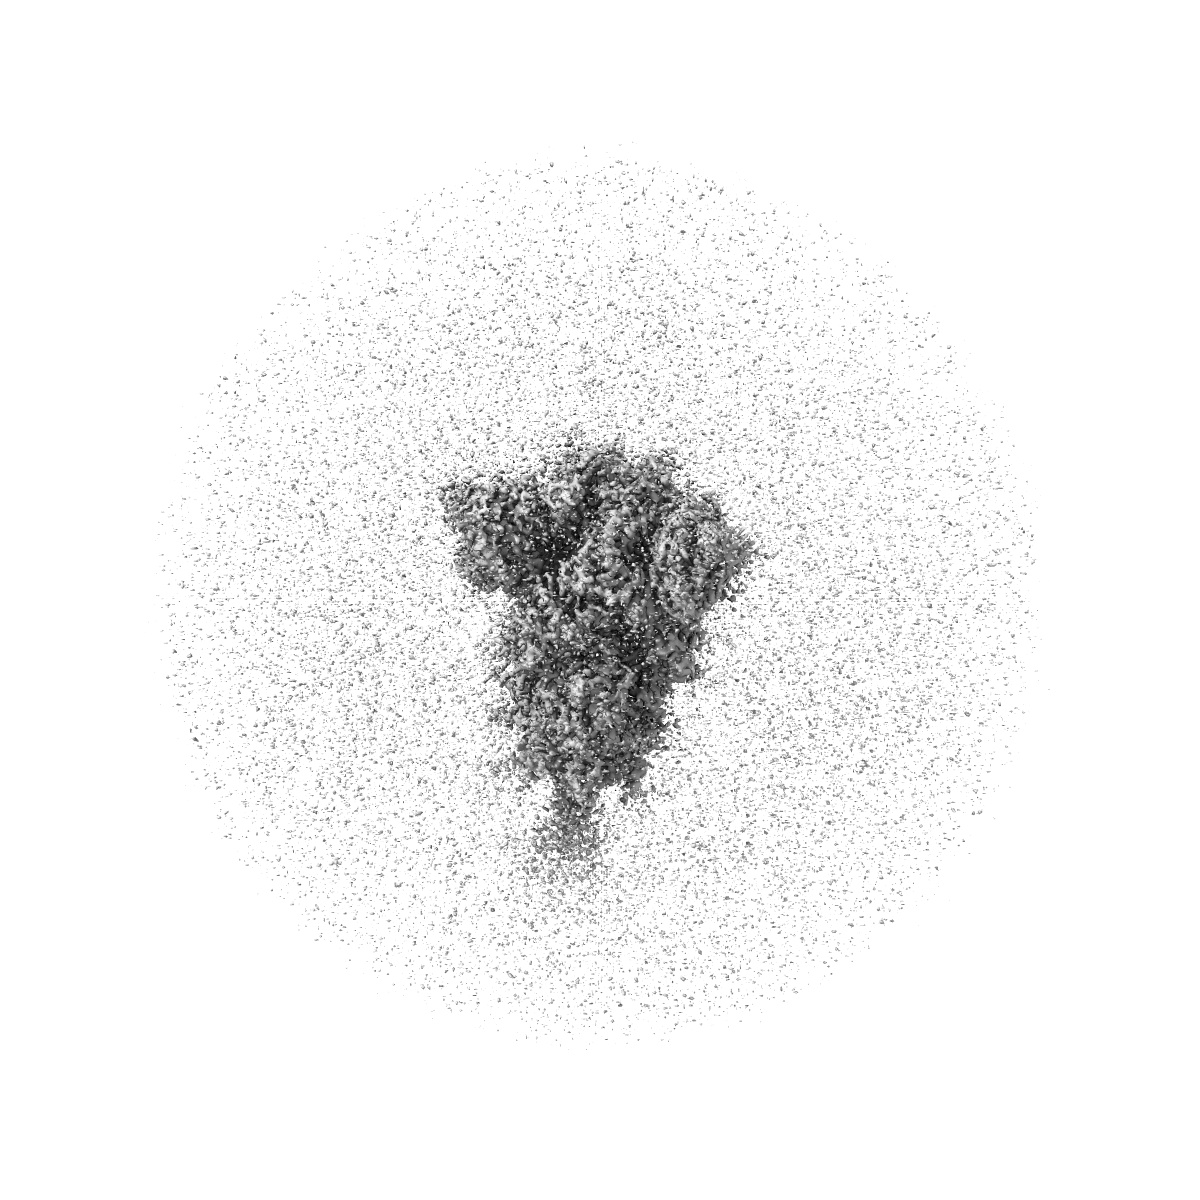

SARS-CoV-2 XBB 1.0 closed conformation.

Single-particle2.9 Å

Sample: Spike XBB.1 RBD DOWN - CLOSED